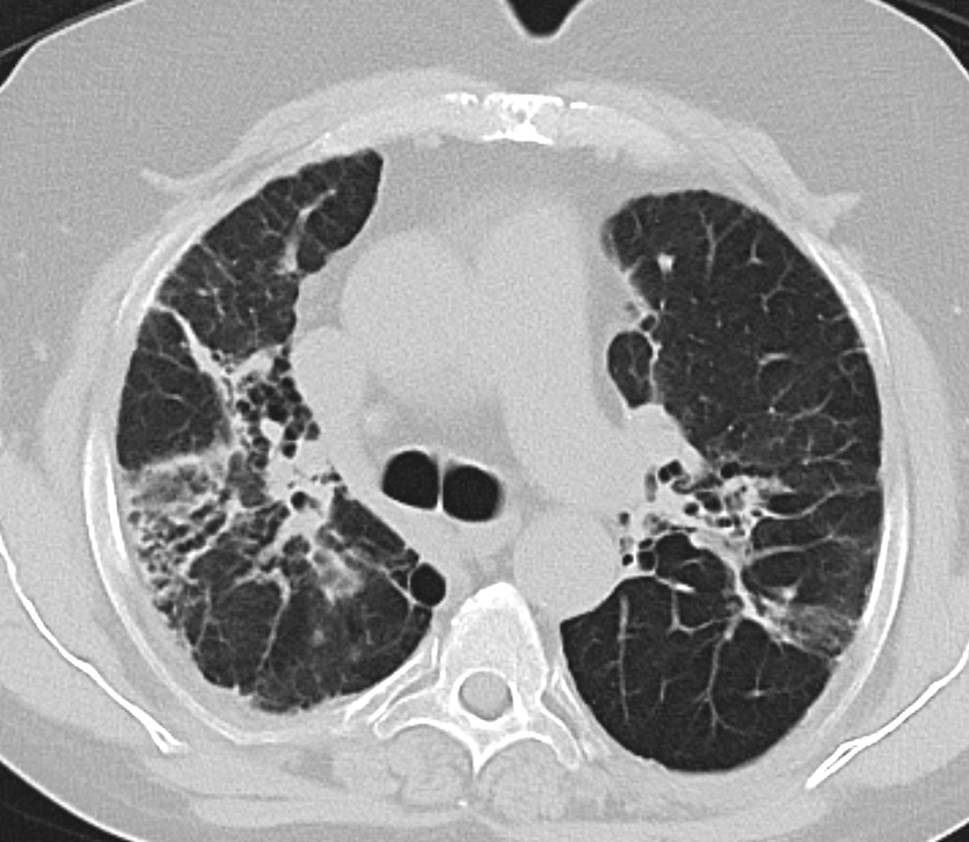

Die Computertomographie (CT) des Thorax ist ein wesentlich präziseres diagnostisches Werkzeug, welches eine detaillierte Darstellung granulomatöser Manifestationen sowie lymphatischer Involvierung intra- und extrathorakal ermöglicht (Abb. 2 und 3).

Abb. 2

Lungensarkoidose mit multiplen Mikronoduli mit perilymphatischer Anordnung (unter Einbeziehung von Pleura und Fissuren). (Quelle: KUK Linz, Universitätsklinik für Innere Medizin 4 – Pneumologie)

In der CT werden Lungenparenchymveränderungen bei Sarkoidose in nichtfibrotische und fibrotische Veränderungen unterteilt, wobei nichtfibrotische Lungenparenchymveränderungen sich als multiple peribronchovaskuläre, perifissurale oder subpleurale Mikronoduli, als multiple größere peribronchovaskuläre Noduli, als verstreute größere Knötchen oder als Konsolidierung als die vorherrschende oder einzige Anomalie manifestieren [17]. Eine Lungenfibrose bei Sarkoidose kann sich mit bronchozentrischen Retikulationen mit oder ohne dichte parenchymale Konsolidierungen, mit oder ohne Kavernenbildung oder als große bronchozentrische Konsolidierungen manifestieren [17]. Vor allem eine bihiläre Lymphadenopathie in Kombination mit mikronodulären Parenchymveränderungen mit perilymphatischer Anordnung (Beteiligung der Pleura und der Fissuren) ist bei entsprechendem klinischem Kontext hochgradig suggestiv für die pulmonale Sarkoidose [18].